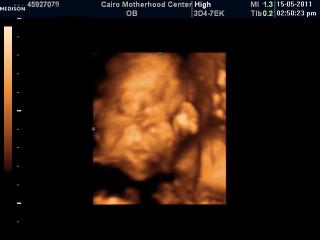

Grej teda to si fakt musíš máknout.Matýsek je teda pěknej cvalík.Ještě že má Simonka 8a půl kilča.Je to můj miláček. a zatím si to spolu užíváme.Jinak já jsem na tom zatím dobře,snad to vydrží napořád.Minulej týden měl prcek 3,5 cm.Za 14 dní jdu na genetiku.